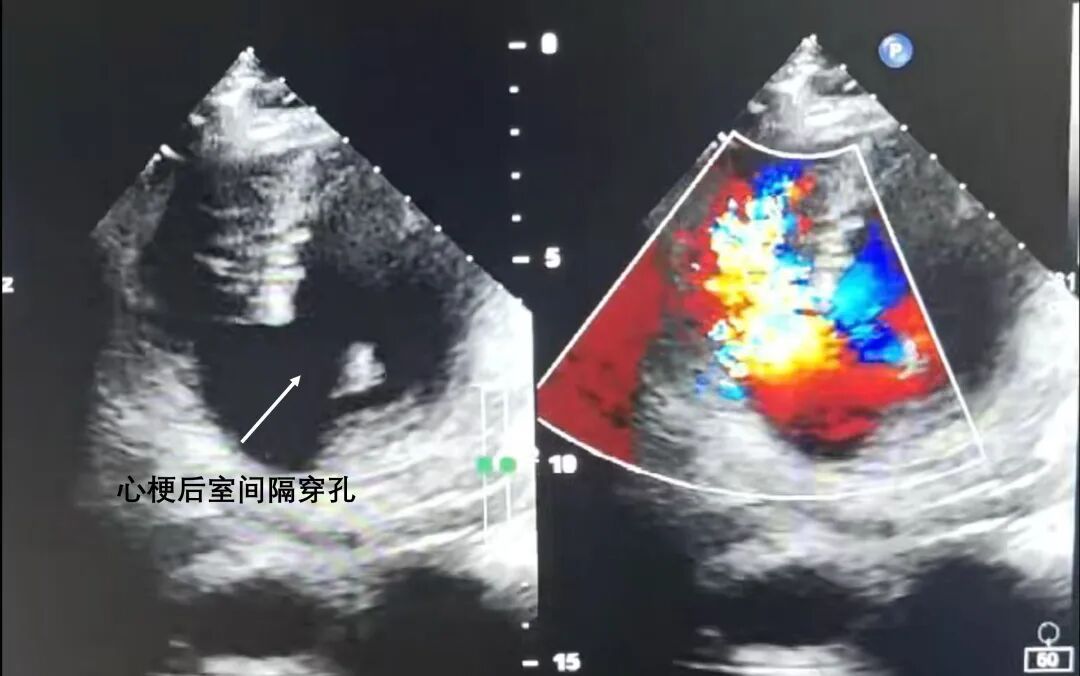

当救护车疾驰至新华医院奉贤院区,急救团队迅速启动绿色通道,全面检查后得出了危急结论:张先生不仅罹患急性心肌梗死,还并发了严重的室间隔穿孔。这一病症,是急性心肌梗死后极具危险性的并发症。

简单来说,心脏的室间隔是分隔左、右心室的心肌壁,急性心梗发作后,部分心肌因缺血坏死,可能导致室间隔破裂,使得左右心室之间出现异常血流通道,大量血液从左心室涌向压力较低的右心室,造成心脏泵血功能急剧下降,进而引发急性心力衰竭,危及生命。

尽管室间隔穿孔在急性心肌梗死患者中的发生率不足0.5%,但保守治疗死亡率高达80%以上;即便选择急性期手术,死亡率也约 30%,足见其凶险程度。张先生的情况更为特殊,他患上的是少见的后室间隔穿孔,且冠脉造影提示合并严重的冠状动脉三支病变,治疗难度和风险更是雪上加霜。

为此,手术团队采用Daggett方法,凭借精湛技术精准暴露手术区域,每一针缝合都力求精细确切。经过长时间的攻坚克难,手术顺利完成。术后即刻超声检查显示,室间隔穿孔修补完整,患者血流动力学趋于稳定。